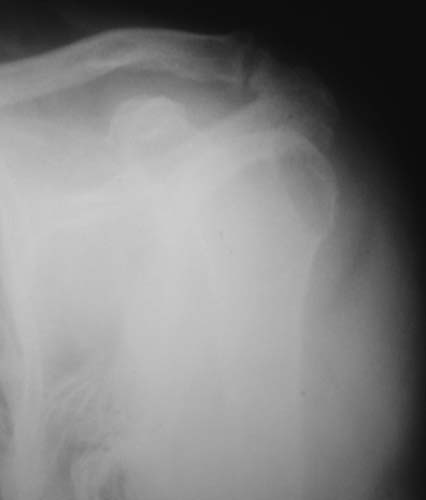

Уважаемые коллеги!Женщина, 60 лет. 3 недели назад упала с упором на отведенную левую руку. Почувствовала боль в левом плечевом суставе. За помощью не обращалась. 2 недели "мази и припарки". Затем - рентгенограмма (r1 и r2), жалобы на боли,ограничение движений...

Активное отведение 80 гр., при пальпации - головка плечевой кости безболезненно вправляется и тут же самостоятельно вывихивается. Наложена косыночная иммобилизация, рентгенография (r3) и МРТ.В нашем диагностическом центре МРТ исследование плечевого сустава выполнено впервые, опыта у нас маловато :(.Вопросы: уточнение диагноза? какие исследования провести? тактика лечения?

Как Вам известно, в некоторых случаях вывихи плеча сопровождаются разрывом ротаторной манжетки, отрывному перелому большого бугорка что приводит к потере наружной ротации и отведения плеча. На представленных рентгенограммах перелом не виден.

МРТ должен показать разрыв манжетки, но признаться я не большой эксперт по чтению МРТ сканов, хотя затемнение, отек мягких тканей по задней поверхности плеча видны Обычные рентгенограммы демонстрируют остеолизис в области большого бугорка.

1. На рентгене - нижний подвывих плеча и очаг остеолиза суставного бугорка с четкими контурами (вдавленный перелом на фоне остеопороза ? доброкачественная опухоль? аваскулярный некроз ? (хотя ни разу не слышал об аваскулярном некрозе плеча..)

Судя по снимкам, речь идTт о типичном случае Hill-Sachs Lesion. По этому поводу я позволю себе некоторый экскурс:

97 % всех вывихов плеча происходит по механизму комбинации отведения, разгибания и наружной ротации (А. Гринспан). В момент вывиха головка плеча ударяет о нижний край гленоида, что ведет к вдавленному или компрессионному перелому одной или обеих структур. Чаще всего, однако, повреждение возникает в задней латеральной области головки плечевой кости на переходе от головки к шейке. Этот диагноз можно выставить на основании рентгеновского снимка в переднезадней проекции с внутренней ротацией плеча. Несколько реже видно повреждение гленоида о передненижний перелом края. То, что мы называем Bankart Lesion. Это повреждение видно на ре. снимке в п.з. проекции при нейтральной позиции плеча. Разумеется хрящевые и мягкотканные повреждения (в смысле Банкарт) мы увидим лучше всего на ЯМР.

Учитывая описанную клинику, речь идTт о комбинации патологии. К сожалению, учитывая качество снимков NMR, я не могу провести достаточно точную верификацию состояния нижнего края гленоида, что впрочем, не меняет рекомендации. Для определения состояния РМ и дополнить исследование УЗИ мягких тканей плеча. В опытных руках достаточно информативное и дешевое исследование.